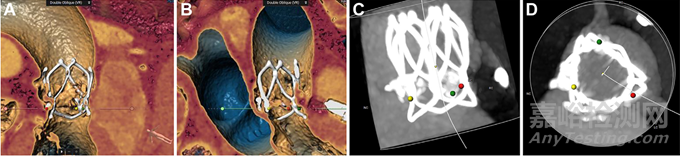

(A至D)產(chǎn)品形態(tài)及與周圍組織的關(guān)系

(A)活體透視顯示主動(dòng)脈根部。(B)鈣化主動(dòng)脈瓣處球囊膨脹。(C)傳遞系統(tǒng)。(D)將參考點(diǎn)與正位環(huán)空對(duì)齊后,逐漸展開瓣膜。(E)確認(rèn)瓣膜位置和冠狀動(dòng)脈血流量。(F)完成閥門部署。(G)即刻血管造影顯示中度瓣膜周圍滲漏。(H) 15分鐘后瓣周滲漏減少至輕度。